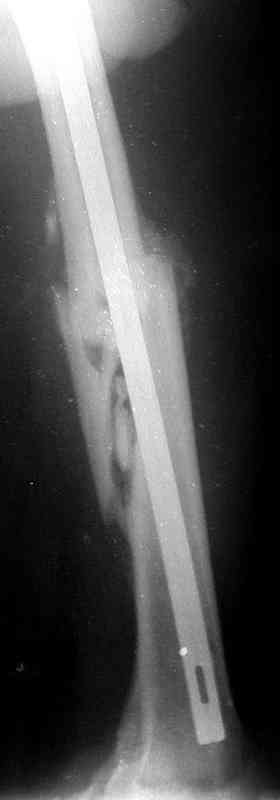

Больной А., 28 лет, поступил в НИИ им. Н.В. Склифосовского 22.12.99 после падения на улице. Жалобы на боли в области левого тазобедренного сустава и левом бедре. Из анамнеза следовало, что 20.06 во время прыжка с парашютом у него возник закрытый оскольчатый перелом средней трети левой бедренной кости со смещением отломков, по поводу чего в одной из ЦРБ Московской области через 3 дня после травмы был произведен открытый интрамедуллярный остеосинтез штифтом типа Кюнчера.

по его наружной поверхности послеоперационный рубец - рана зажила первичным натяжением. При измерении длины бедер обнаружено укорочение левого бедра на 4,5 см. На рентгенограммах этого бедра: ось конечности правильная, отмечается захождение основных костных фрагментов по длине, проксимальный конец штифта выступает слишком медиально и высоко относительно большого вертела, периостальная мозоль незначительна.22.12 - через 6 месяцев после операции, произведенной в ЦРБ, нами по поводу замедленно консолидирующего перелома левой бедренной кости с ее абсолютным укорочением под наркозом произведена операция: удаление штифта, закрытый блокирующий интрамедуллярный остеосинтез перелома левого бедра штифтом без рассверливания (UFN) длиной 40 см, диаметром 10 мм с блокированием только проксимальных отверстий (динамический остеосинтез). Наложен аппарат Илизарова на 4 полукольцах с целью удлинения укороченного бедра. Послеоперационное течение без особенностей. Ежедневно осуществляли дистракцию отломков на 1 мм. Через 3 недели после операции больной выпи-сан на амбулаторное лечение с продолжением дистракции отломков. В течение 1,5